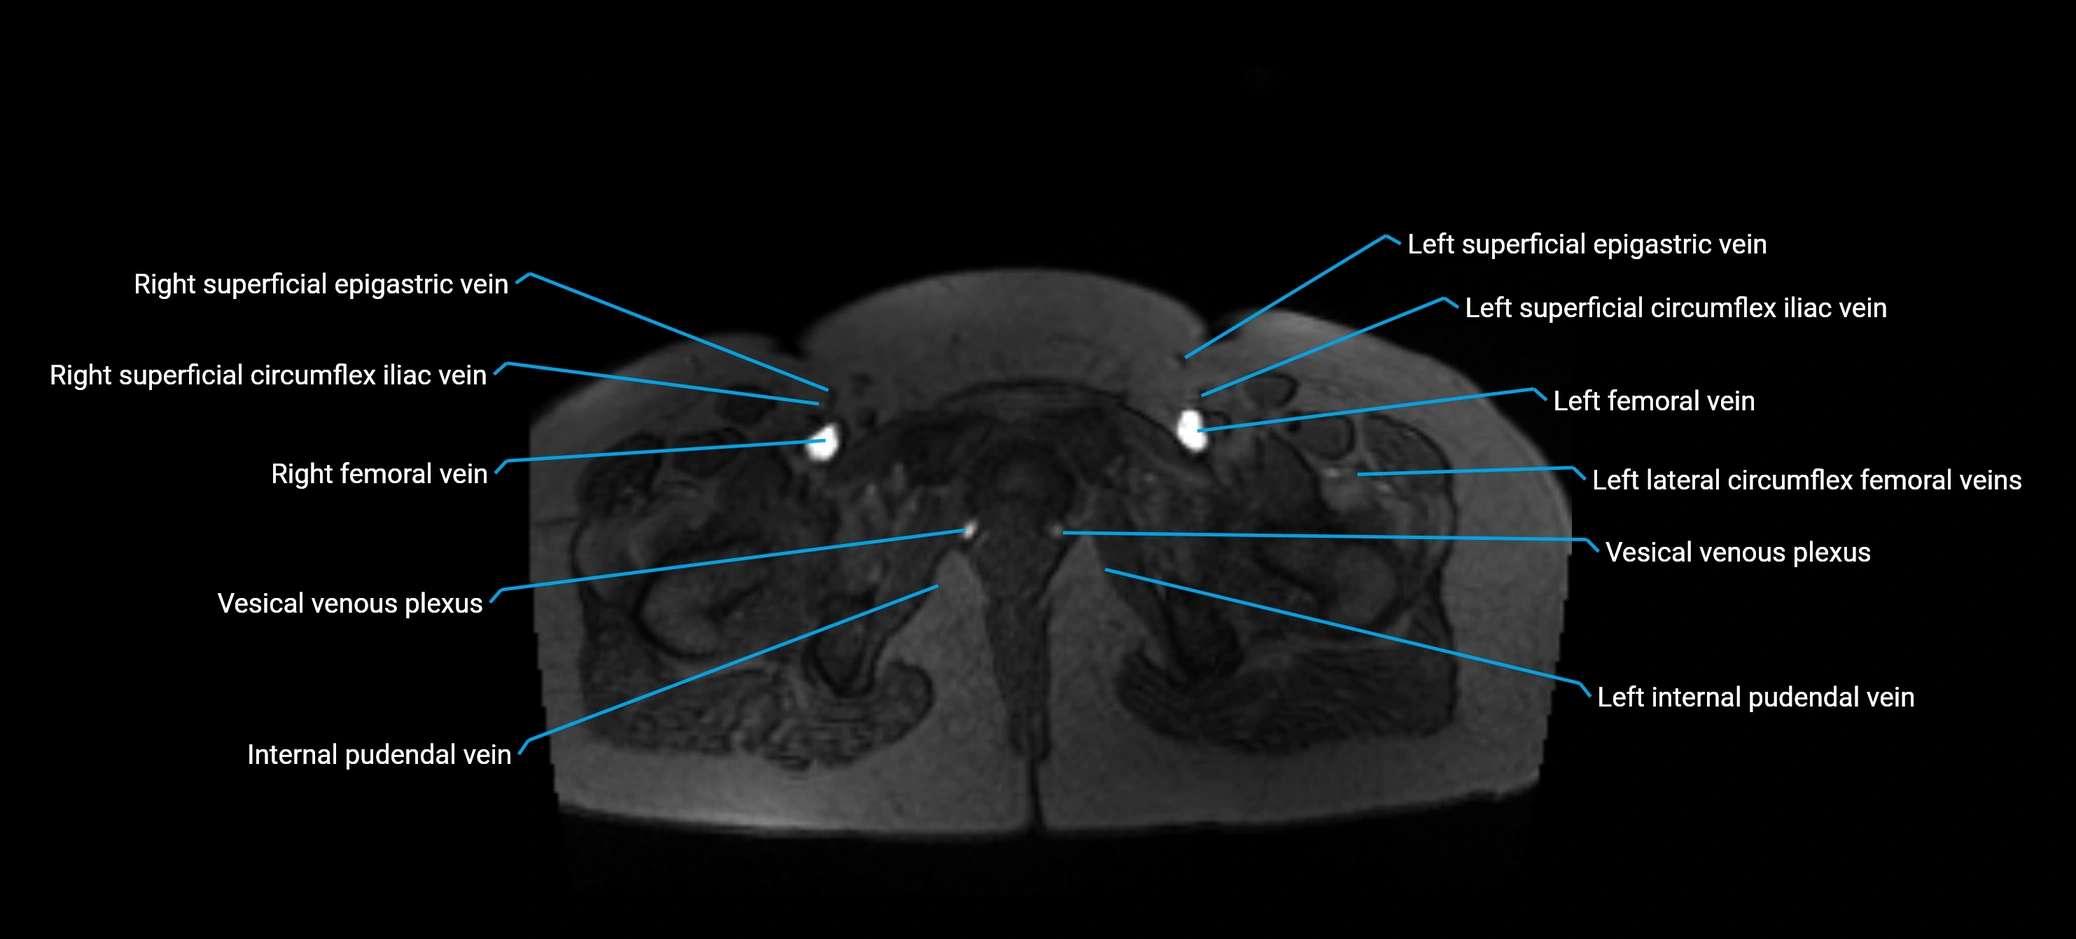

MRI image

image